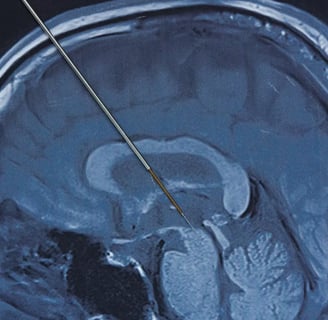

Sin embargo en el 2020 -inicios- un grupo de investigadores decidieron cambiar la perspectiva de los ensayos predecesores. Implantando 2 electrodos de DBS a cada lado de su cerebro, en las zonas convencionalmente asociadas a los síntomas de la depresión, a un primer voluntario. Adicionalmente 5 electrodos temporales fueron puestos en cada lado de su cerebro para monitorear su actividad en las regiones vinculadas con el estado de ánimo y los procesos cognitivos.

Durante la cirugía para implantarle los electrodos al voluntario, quien se identificó como John, tuvieron que despertarlo para poder realizarle algunas preguntas de control, mientras el equipo de cirujanos iban realizando prueba con los electrodos en su cerebro.

En el artículo John comenta: “Entonces le dieron a un punto y dije: ‘de hecho me siento otra vez en linea’ […] La depresión es como cargar un pesos constante sobre tu alma. Cuando ellos (los cirujanos) tocaron ese perfecto pequeño punto, el peso se levantó”.